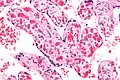

Very high mag.

Chorangiosis is a placental pathology characterized by an abundance of blood vessels within the chorionic villi.

It is diagnosed by a microscopic examination of the placenta.

Commonly used criteria from Altshuler[2][3] are: "a minimum of 10 villi, each with 10 or more vascular channels, in 10 or more areas of 3 or more random, non-infarcted placental areas when using a ×10 ocular." The Altshuler criteria are not theoretically rigorous, as they do not define the area. Normal villi have up to five vascular channels.[3]